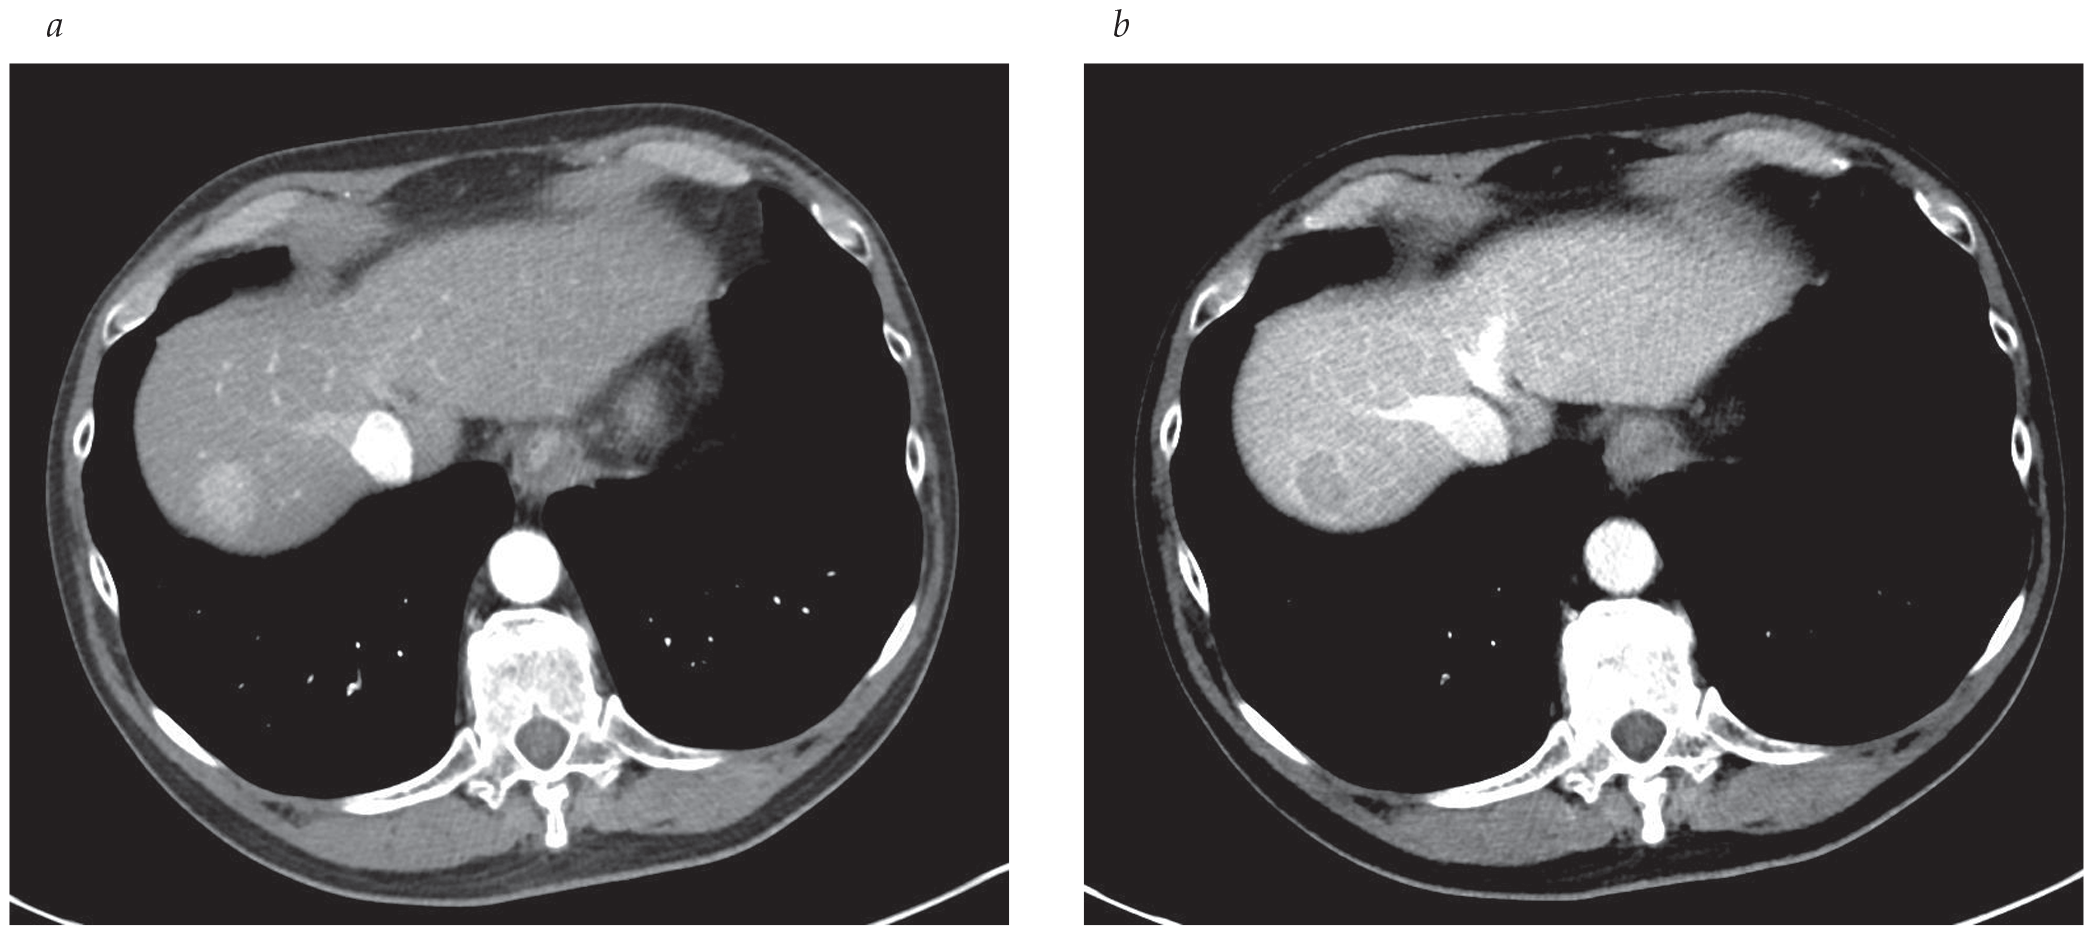

- The Liver Imaging Reporting and Data System for hepatocellular carcinoma (HCC) provides a standardized reporting mechanism for imaging findings and correlation with suspicion for HCC.

- Portal vein embolization is being increasingly used for functional future liver remnant volume, with less than 40% in patients undergoing major hepatic resection.

- Advances in locoregional liver therapy provide additional treatment options for unresectable liver malignancies.